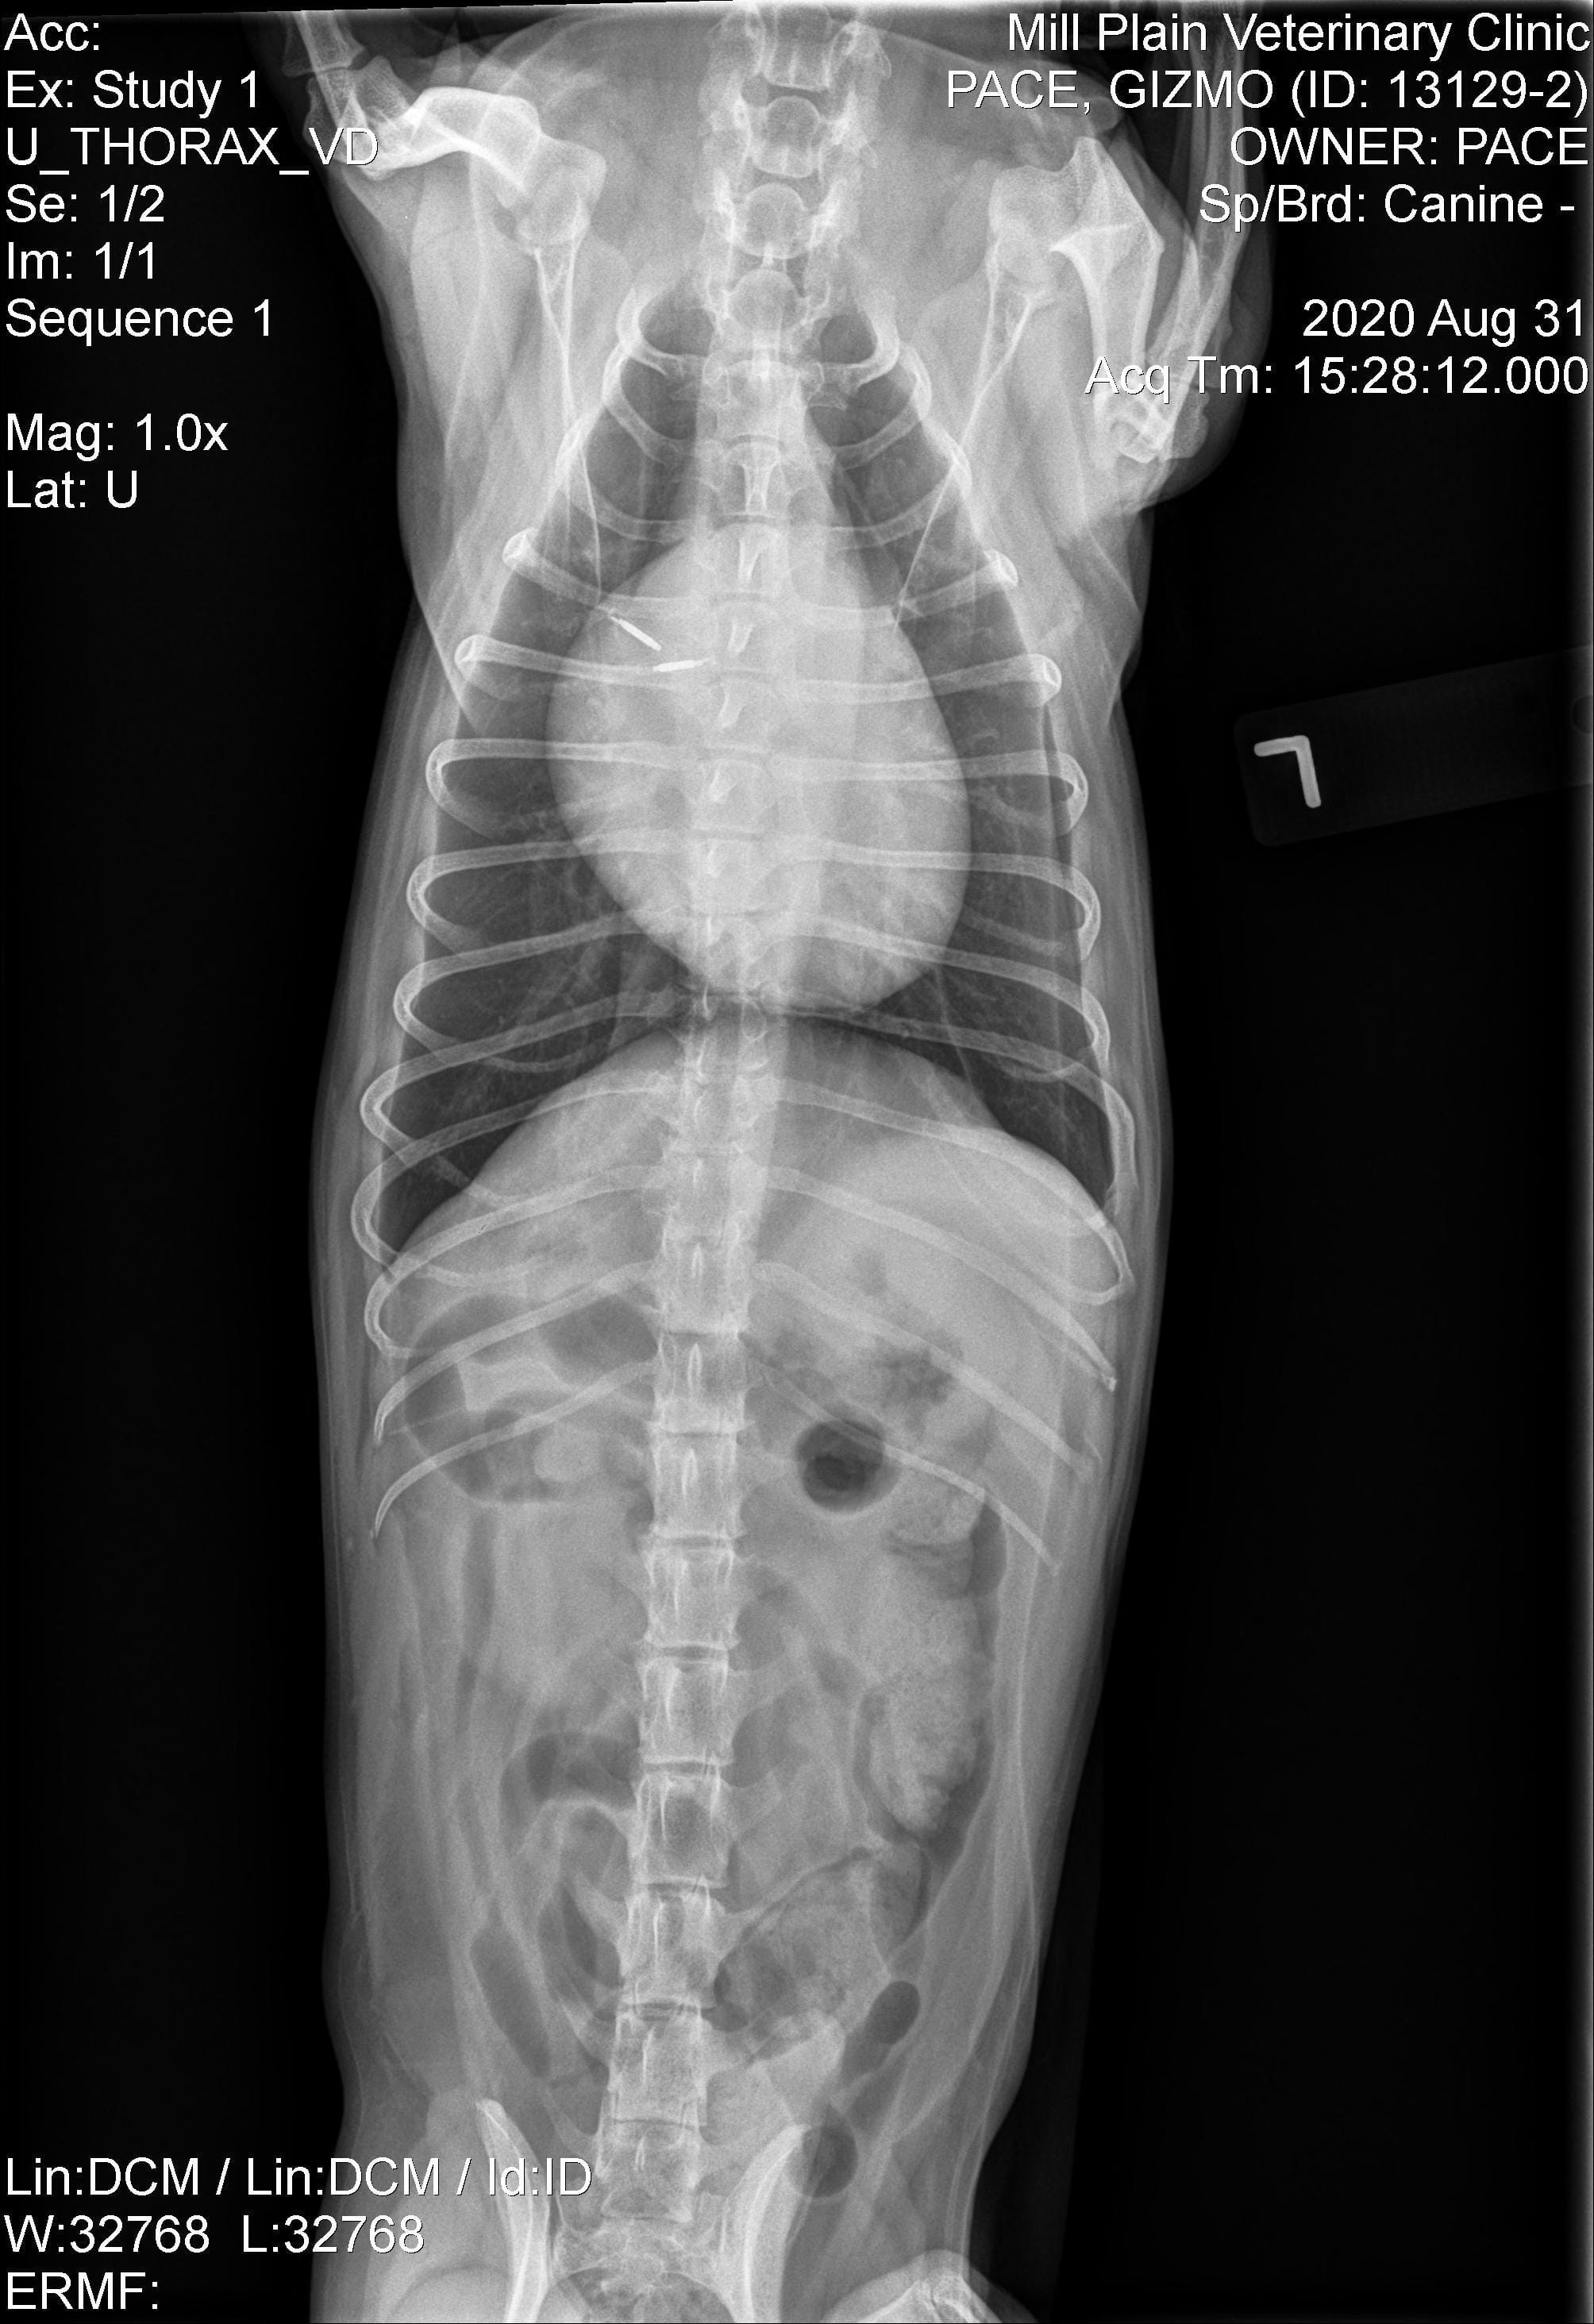

A dog I'm considering adopting has a Grade IV to V heart murmur that was never treated from what we can tell. He came up from Florida and didn't have an records on this. Gizmo was then seen by a veterinarian. The X-ray showed enlargement of his heart so he was put on Vetmedin and Enalapril. I'm trying to find out how his conditions may affect his daily life, and life expectancy, as well as the possible financial implications of adopting this dog.